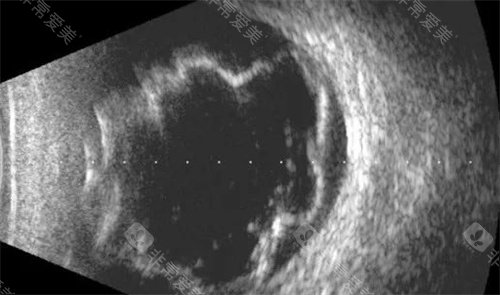

初诊准备:携带身份证、卡、既往检查报告。初诊时解医生会进行详细眼底检查,包括OCT、眼底荧光造影等,超全评估病情。

68岁的张阿姨是解医生的典型患者。初诊时右眼视力仅0.1,确诊为湿性老年黄斑变性。

经过3个月治疗,视力提升至0.5,黄斑区水肿明显消退。